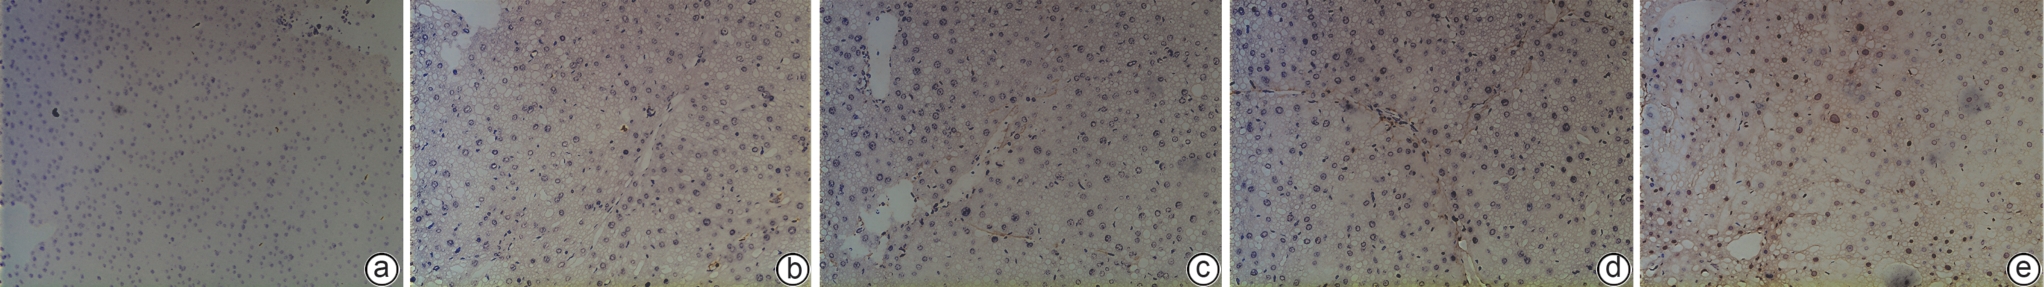

黄芪甲苷Ⅳ对四氯化碳诱导的肝纤维化小鼠模型的影响及其作用机制

朱宛春, 邱嘉昊, 崔钰, 张伊婧, 尚志, 高月求, 黄凌鹰

2026, 42(3): 608-617. DOI: 10.12449/JCH260316

摘要:

目的  明确黄芪甲苷Ⅳ(AS-Ⅳ)在体内外的肝脏保护和抗肝纤维化作用,并探讨其在抗肝纤维化中的作用机制。  方法  动物实验:将C57BL/6J小鼠分为对照组、模型组、AS-Ⅳ低剂量组(20 mg/kg)和AS-Ⅳ高剂量组(80 mg/kg)。通过腹腔注射四氯化碳6周构建肝纤维化模型,从第3周开始,AS-Ⅳ组分别予以AS-Ⅳ 20 mg/kg、80 mg/kg灌胃,给药4周后检测血清丙氨酸氨基转移酶(ALT)、天冬氨酸氨基转移酶(AST)水平,以及血清透明质酸(HA)、层粘连蛋白(LN)、Ⅲ型前胶原(PⅢNP)及Ⅳ型胶原(Col-Ⅳ)水平;苏木精-伊红染色、天狼星红染色和马松染色观察肝组织病理及胶原沉积情况;定量逆转录聚合酶链反应检测肝组织Acta2、Col1a1、Col3a1的mRNA表达;Western Blot法检测肝组织α-平滑肌肌动蛋白(α-SMA)、Ⅲ型胶原蛋白(Col-Ⅲ)、磷酸化磷脂酰肌醇3-激酶(pPI3K)/PI3K、磷酸化蛋白激酶B(pAkt)/Akt蛋白表达水平;运用转录组学技术对小鼠肝组织进行测序分析,筛选差异基因并进行生物信息学分析。细胞实验:采用转化生长因子β(TGF-β)诱导LX-2细胞活化,进一步使用PI3K抑制剂LY294002以及PI3K激动剂740 Y-P对细胞进行干预,设对照组、模型组、AS-Ⅳ组、LY294002组、AS-Ⅳ+740 Y-P组,36 h后收集细胞。检测LX-2细胞α-SMA、Col-Ⅲ、pPI3K/PI3K和pAkt/Akt蛋白表达的变化,以及Acta2、Col1a1和Col3a1的mRNA相对表达量。计量资料多组间比较采用单因素方差分析,进一步两两比较使用LSD-t检验。  结果  动物实验:与模型组相比,AS-Ⅳ治疗组小鼠血清ALT、AST、HA、LN、PⅢNP和Col-Ⅳ水平均显著降低(P值均<0.01);肝组织Acta2、Col1a1和Col3a1的mRNA表达均显著降低(P值均<0.05);与模型组相比,治疗组小鼠肝组织α-SMA、Col-Ⅲ、pPI3K和pAkt(Ser473)的蛋白表达均显著减少(P值均<0.05)。细胞实验:与对照组相比,TGF-β诱导后模型组细胞α-SMA、Col-Ⅲ、pPI3K和pAkt蛋白表达水平显著升高(P值均<0.05);与模型组比较,AS-Ⅳ组细胞α-SMA、Col-Ⅲ、pPI3K和pAkt(Ser473)蛋白表达水平显著降低(P值均<0.05),LY294002组细胞pPI3K蛋白表达,以及Acta2、Col1a1和Col3a1的mRNA相对表达量亦显著降低(P值均<0.05)。而予740 Y-P干预后,与AS-Ⅳ组相比,pPI3K蛋白表达及Acta2、Col1a1和Col3a1的mRNA相对表达量均明显升高(P值均<0.05)。  结论  AS-Ⅳ通过抑制肝星状细胞活化从而改善肝纤维化,其作用机制可能与抑制PI3K/Akt信号通路有关。